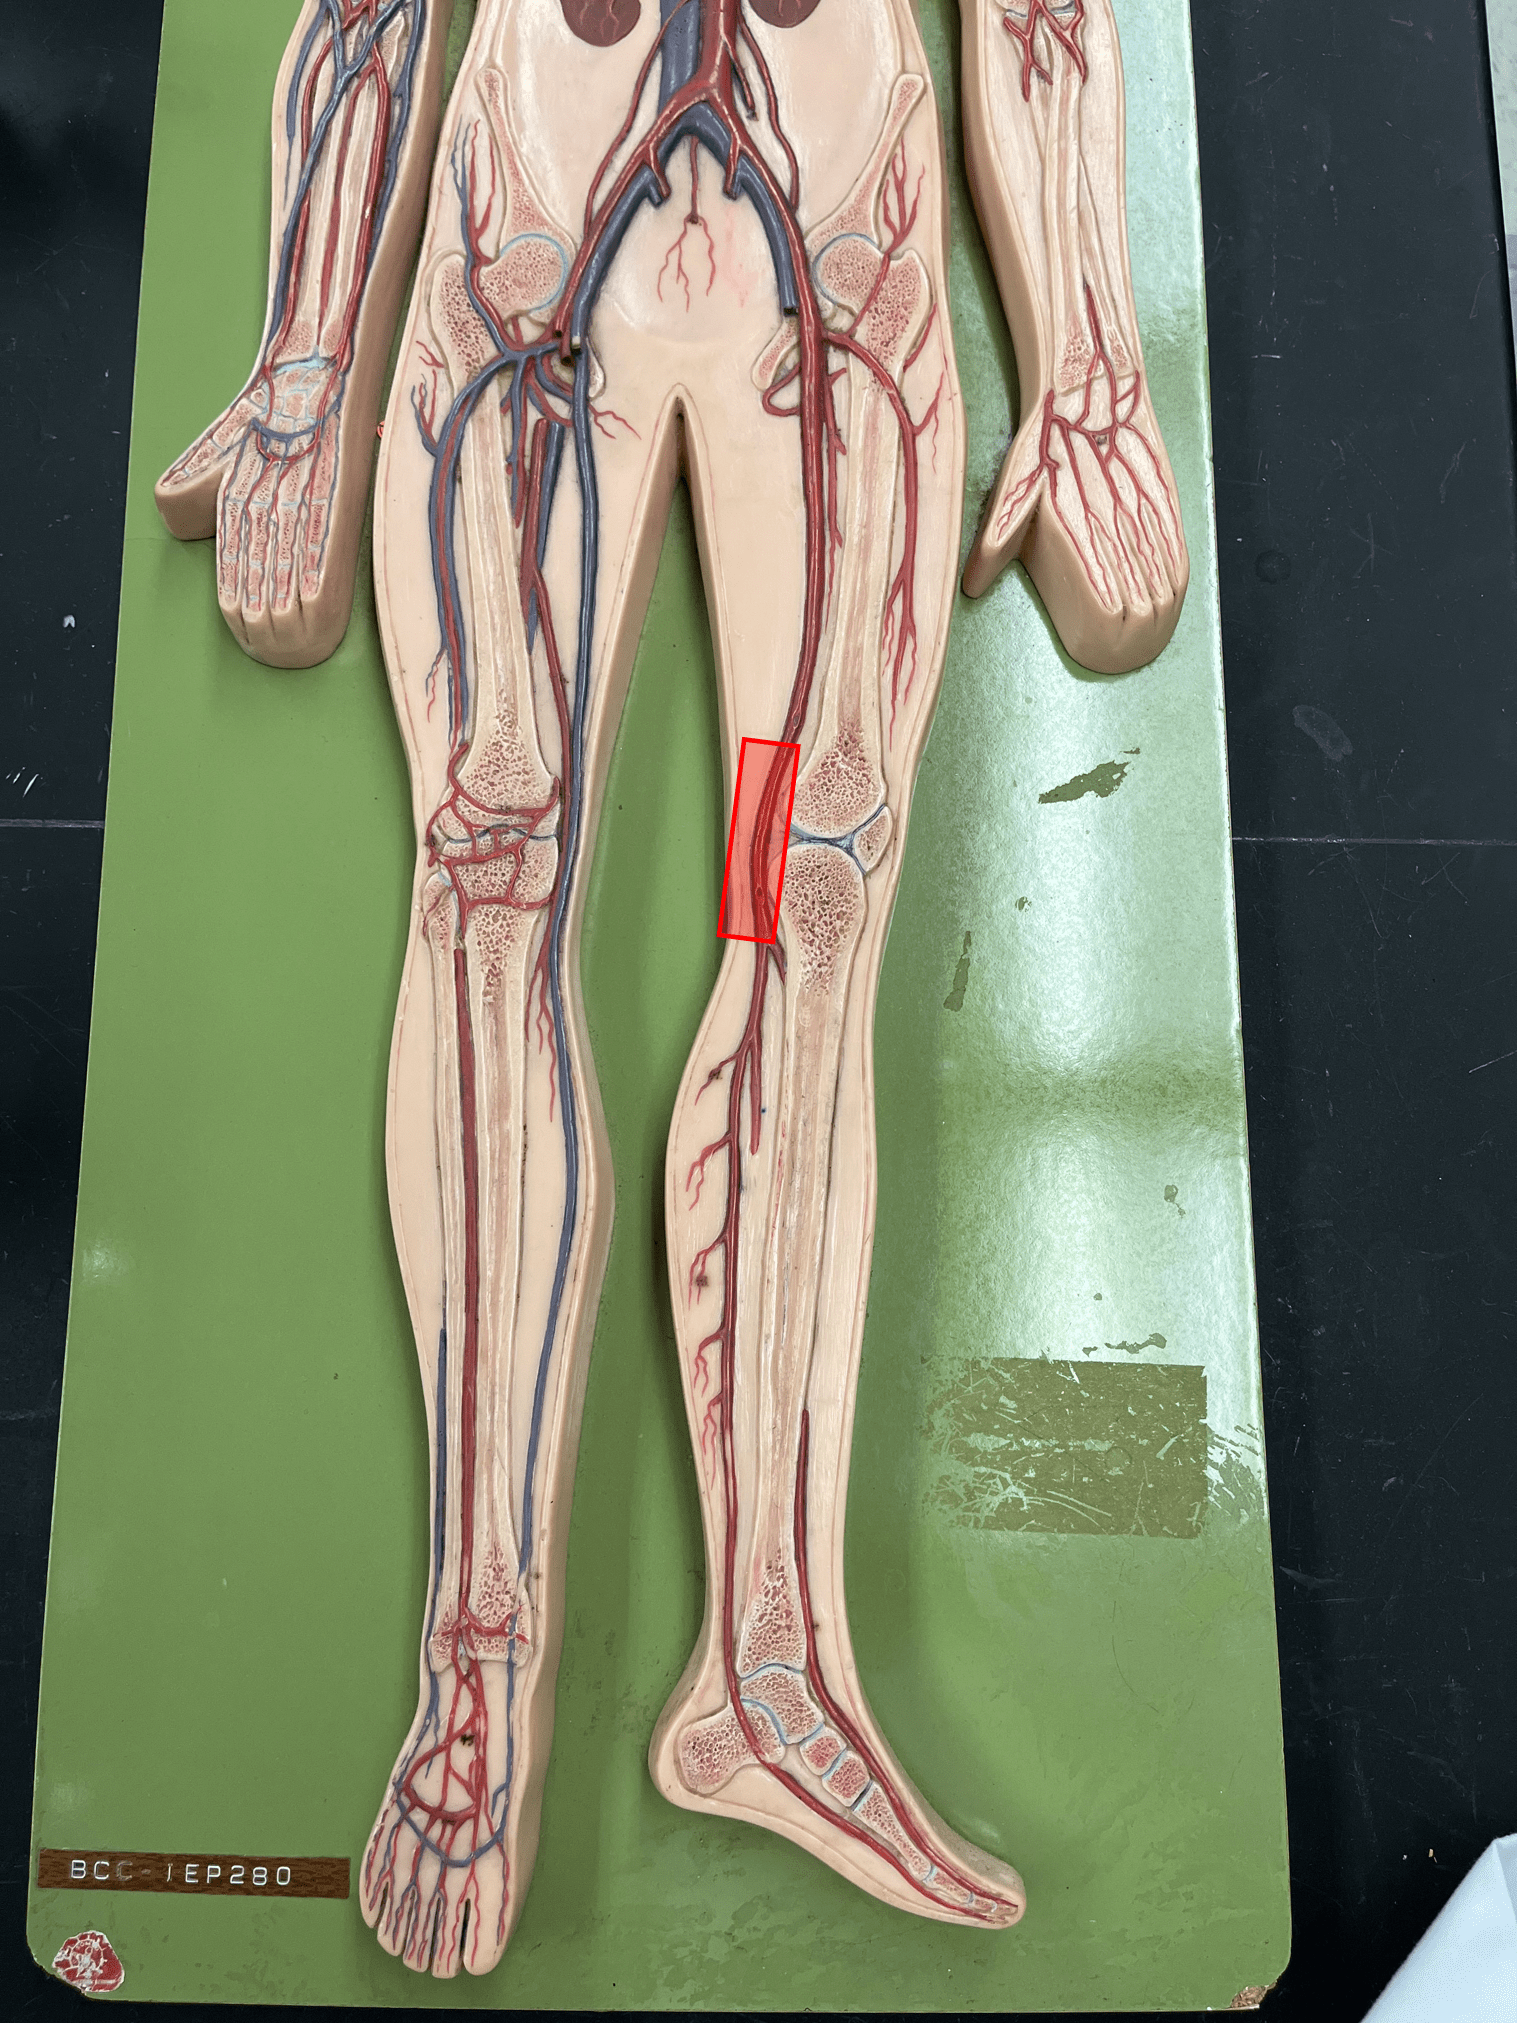

• Part of the tunica interna.

• Composes a smooth inner surface of the vessel.